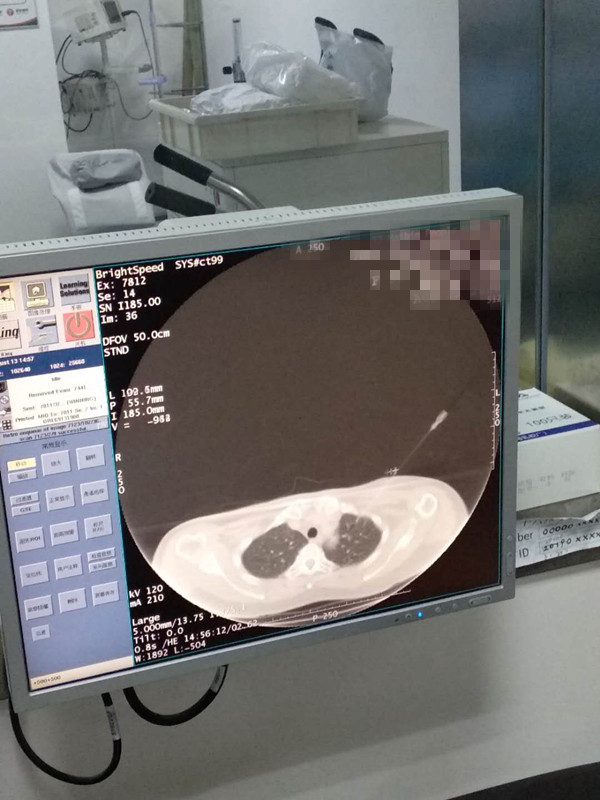

50岁肺部氩氦刀冷冻消融

发布人:美国氩氦刀技术官方网站    发布时间:2020/8/17 16:21:20